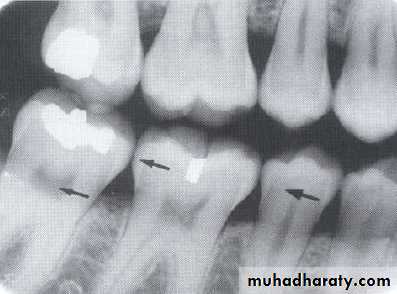

Bitewing radiograph. This radiograph shows (1) large occlusal caries, (2) radiolucent lines or mach band effect (an optical illusion caused by overlapped enamel), (3) interproximal caries, and

(4) cervical burnout